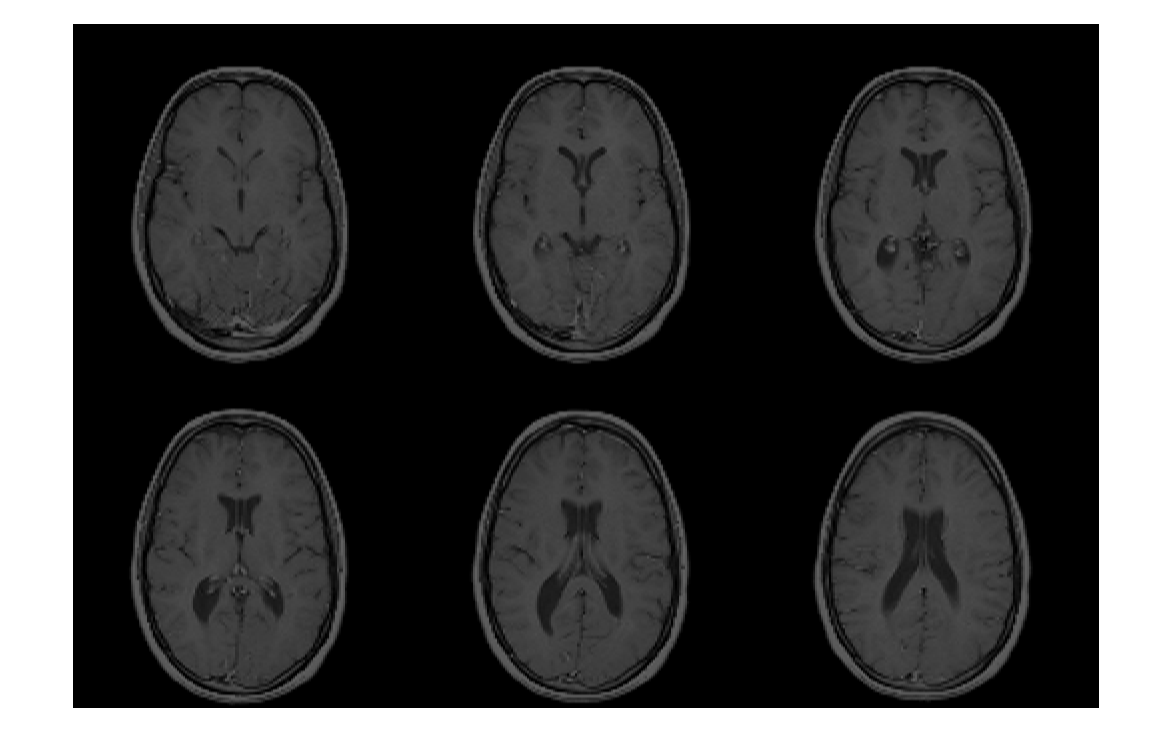

Считайте данные изображения из файла Analyze 7.5.

X = analyze75read('brainMRI');

Просмотрите данные. Во-первых, потому что формат Analyze 7.5 использует радиологическую ориентацию (LAS), инвертируйте данные для отображения правильного образа в MATLAB.

X = flip(X);

Затем измените данные, чтобы создать массив, который может быть отображен с помощью montage. Выберите системы координат 12 - 17.

Y = reshape(X(:,:,12:17),[size(X,1) size(X,2) 1 6]);

montage(Y);